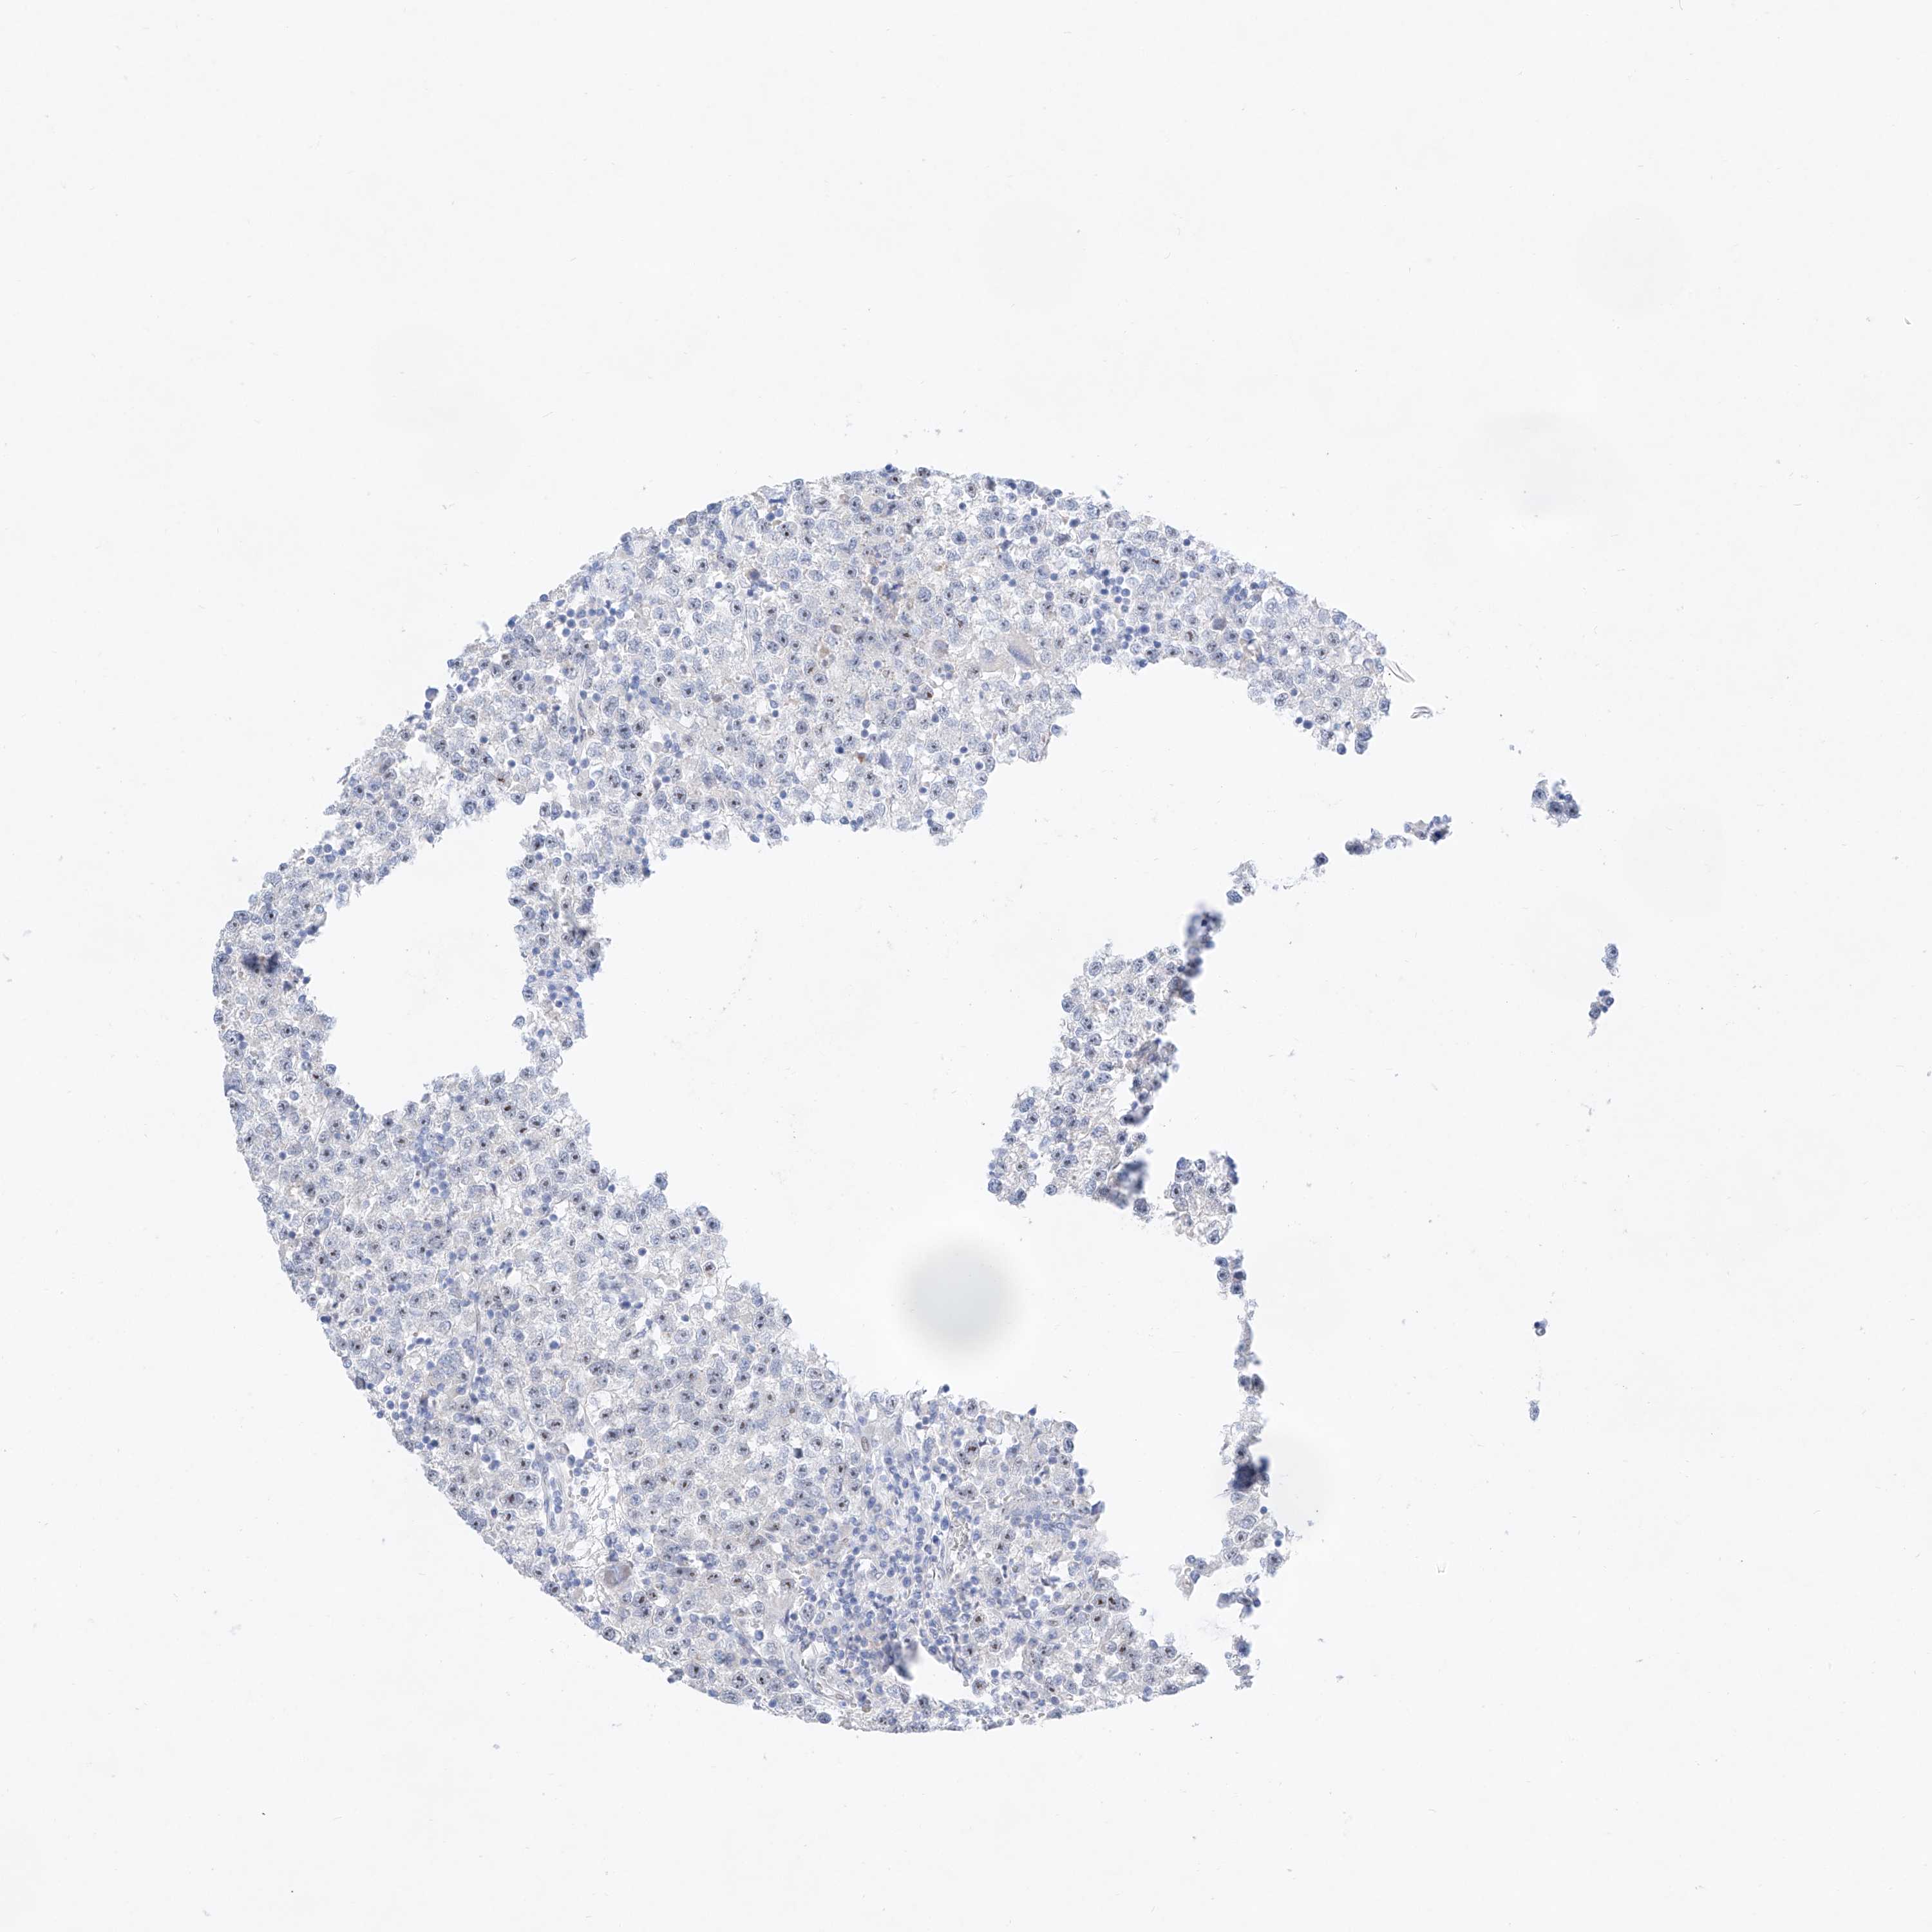

Testis cancer

Human pathology